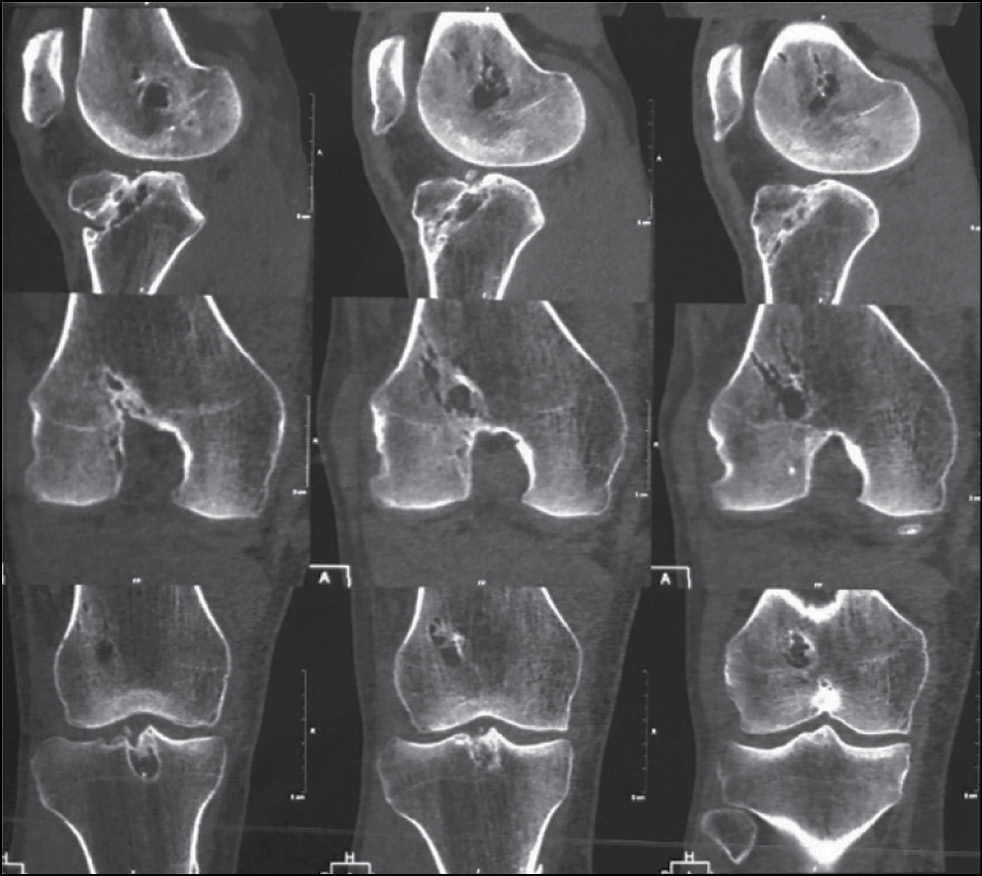

The preoperative examination included X-ray images of the knee joint in two views, namely, anteroposterior and lateral in full lower leg extension in the knee joint. Before the surgery, CT of the knee joint was obligatory. CT images were used to determine the topical location of the femoral and tibial channels, their enlargement, narrowing of the joint cavity, and location and type of the fixing structure (Fig. 13).

Fig. 13. Preoperative CT-scans.

Patients’ medical records were evaluated to determine the size of the intraosseous channels and type of the fixation structures. The correction was made by comparing the diameter measured with CT and the true diameter of the intraosseous channel. In all cases, CT revealed an increase in the diameter of the intraosseous channels and a violation of their topical location.